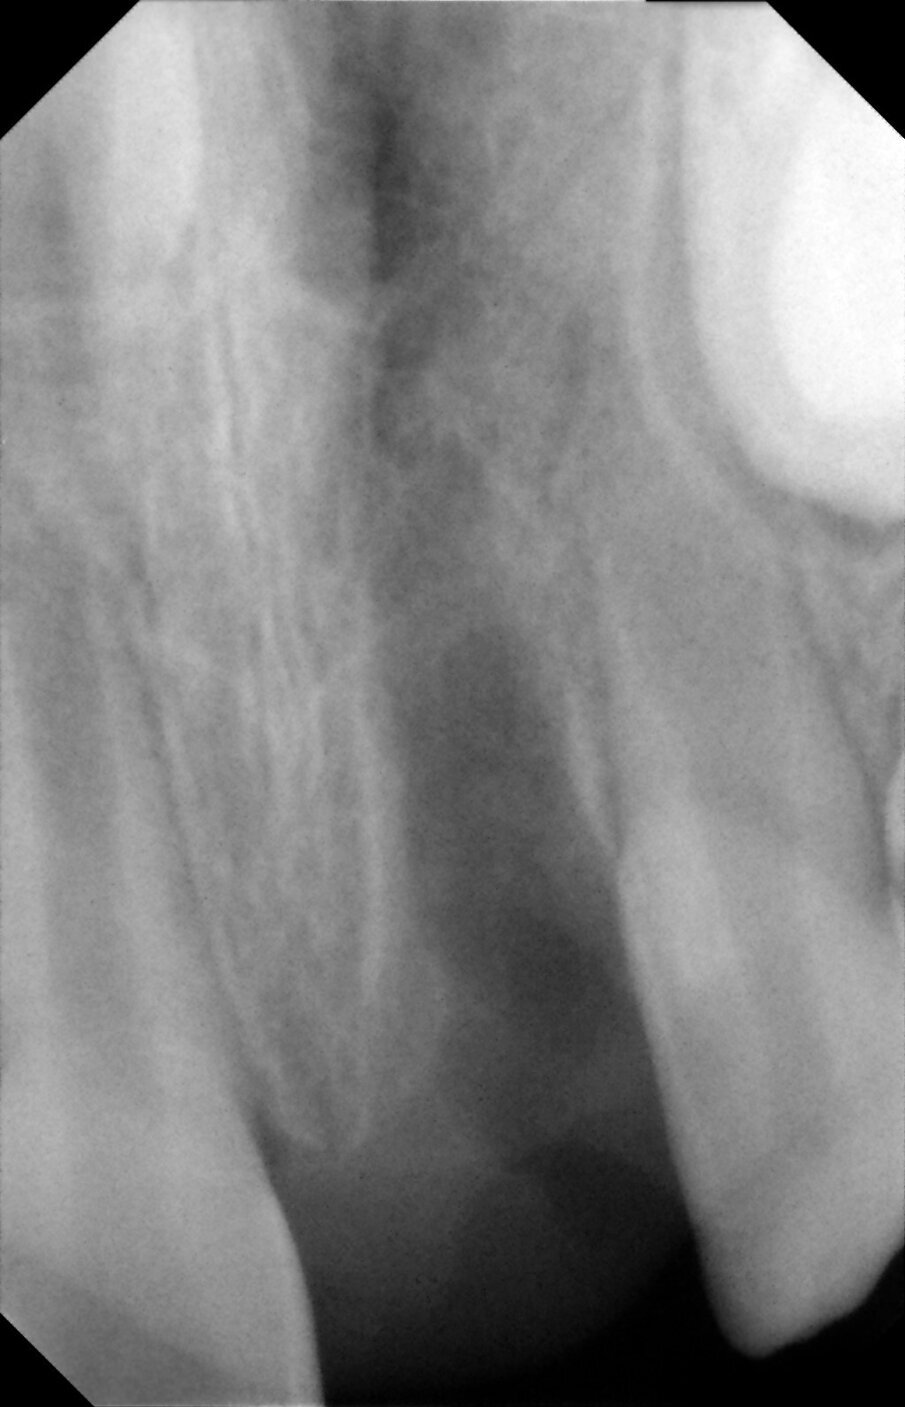

Periapical views of the upper maxillary incisors were obtained to rule out any root fractures (See Figures 4 a & b) revealed immature roots of teeth # 12, 11, 22, no root fractures and an inverted supernumerary apical to 11 and an empty socket of 21. There was no need for soft tissue radiographs as no tooth fragments were missing and the tooth was accounted for.

Figures 4a. Empty socket of 21 due to its avulsion. Notice the immature apices of 12, 11 and 22. In addition there was a supernumerary tooth/mesiodens

Figures 4b. Empy socket of 21 due to its avulsion. Notice the immature apices of 12, 11 and 22. In addition there was a supernumerary tooth/mesiodens